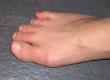

Figure 1

Hallux valgus with a hallux valgus angle of 20° and pain from pressure on the bunion medially